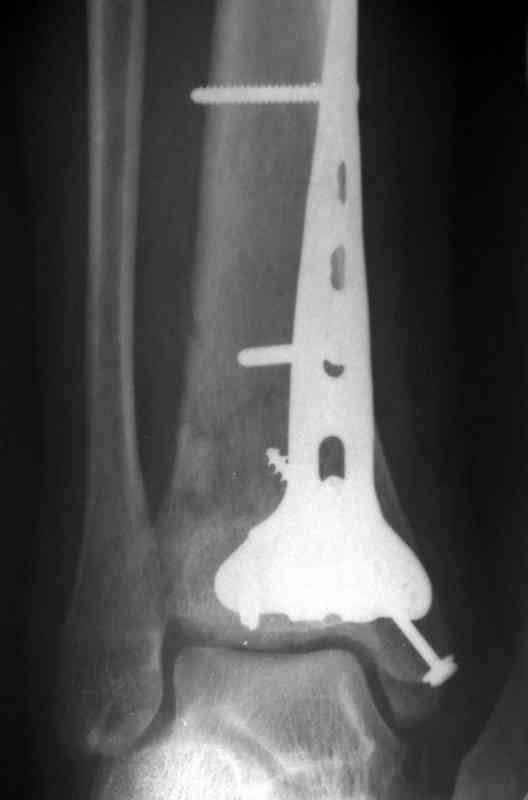

На рентгенограммах типичный перелом пилона по типу С-3. есть опыт до 100 открытых опреаций у нас в клинике. 20 примерно в год. Принцип один -все внутрисуставные переломы нуждаются в открытой репозиции и внутренней стабильной фиксации. При поступлении КТ не надо, так как получается только нагромождение костей. Истинной картины нет. Главное восстановить длину малоберцовой кости - это ключ к успеху. При поступлении меньше всего надо думать о сосудистых расстройствах, т.к. сама операция и репозиция даже сначала частичная даёт улучшение сосудитых нарушений. Причём очень быстро. Операция в 2этапа. При поступлении доступ позади наружной лодыжки, причём обязательно. После этого репозиция малоберцовой кости и фиксация пластиной 1/3 трубки под винт 3,5. Дренаж и любой аппарат наружной фиксации. Затем после спадения отёка на 5-7-10 день аппрат снимается и дугообразный разрез спереди от медиальной лодыжки 10-12 см. Главной чтобы расстояние между 1 и вторым разрезом было не меньше 7-8 см. Тогда не будет некрозов лоскутов. Таранная кость используется как матрица на неё укладываются отломки и фиксируются пицами. Ренг-контроль. Отломки лежат все отдельно, но ничего не высыпется. При переломах С-3 всегда нужна костная пластика (из крыла). Фиксация пластиной лист клевера простой или LCP. Гипс не нужен. Дренаж до 48 часов. Операция длится 3-4 часа обязательно без жгута. Посылаю примерно такой же случай.

Послала ещё два снимка, если не пройдут, пошлю ещё. Дрягин. Если есть вопросы, готов ответить.